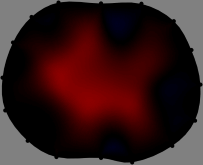

Figs. 3 and 4 compare the performance of the proposed FER method in (20) with the standard regularized least-squares method ((19) when is the identity matrix). The regularization parameter of the standard method was heuristically chosen for its best performance, and the parameter of the FER method was set to be one of three different values . The injection current was 1 mA at 100 kHz, and the frame rate was 9 frames per second. The reference frame at was obtained from the maximum expiration state. The measured data, , represent the voltage differences between each time and . The blue regions, which denote where conductivity decreased by inhaled air, increased during inspiration and decreased during expiration. The FER method with was clearly more robust than the standard method that produced more artifacts originated from the inversion process.